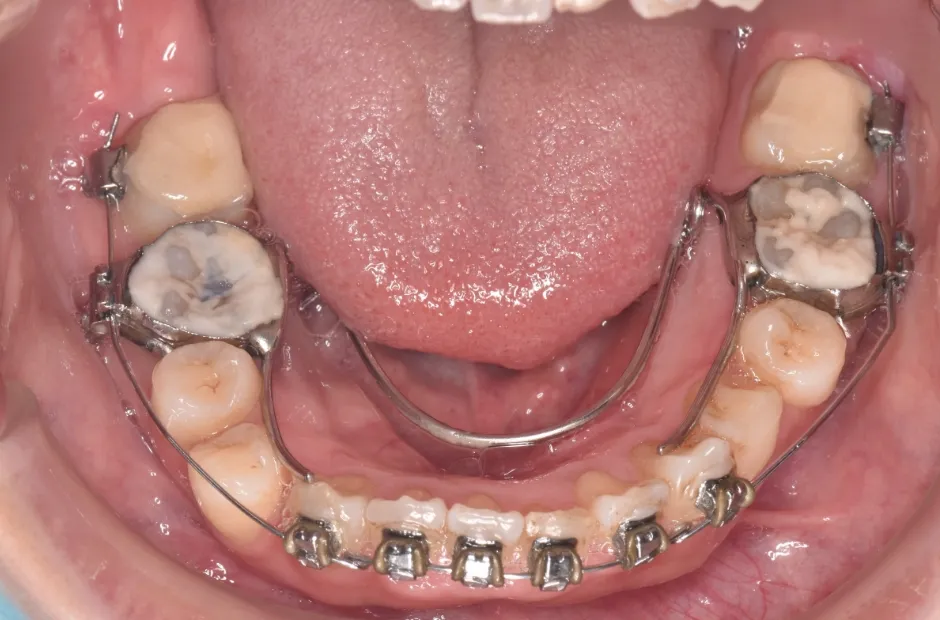

開咬

| 診断名・主訴 | 開咬 |

|---|---|

| 年齢・性別 | 18歳・男性 |

| 治療期間・回数 | 1年 12回 |

| 治療に用いた主な装置 | ロール付きリンガルアーチ |

| 抜歯部位 | なし |

| 治療費 | 70万円(税抜) |

| リスク・副作用 | 装置による違和感・疼痛・歯肉退縮・歯根吸収・虫歯のリスクなど |

治療中